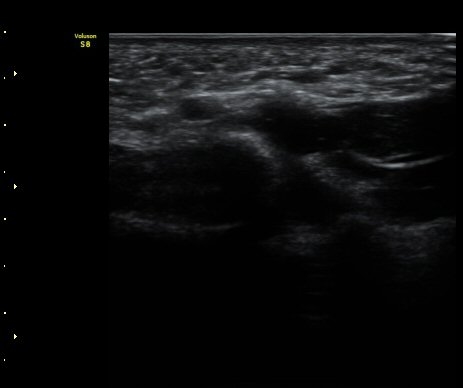

ÃÊÀ½ÆÄ °Ë»ç